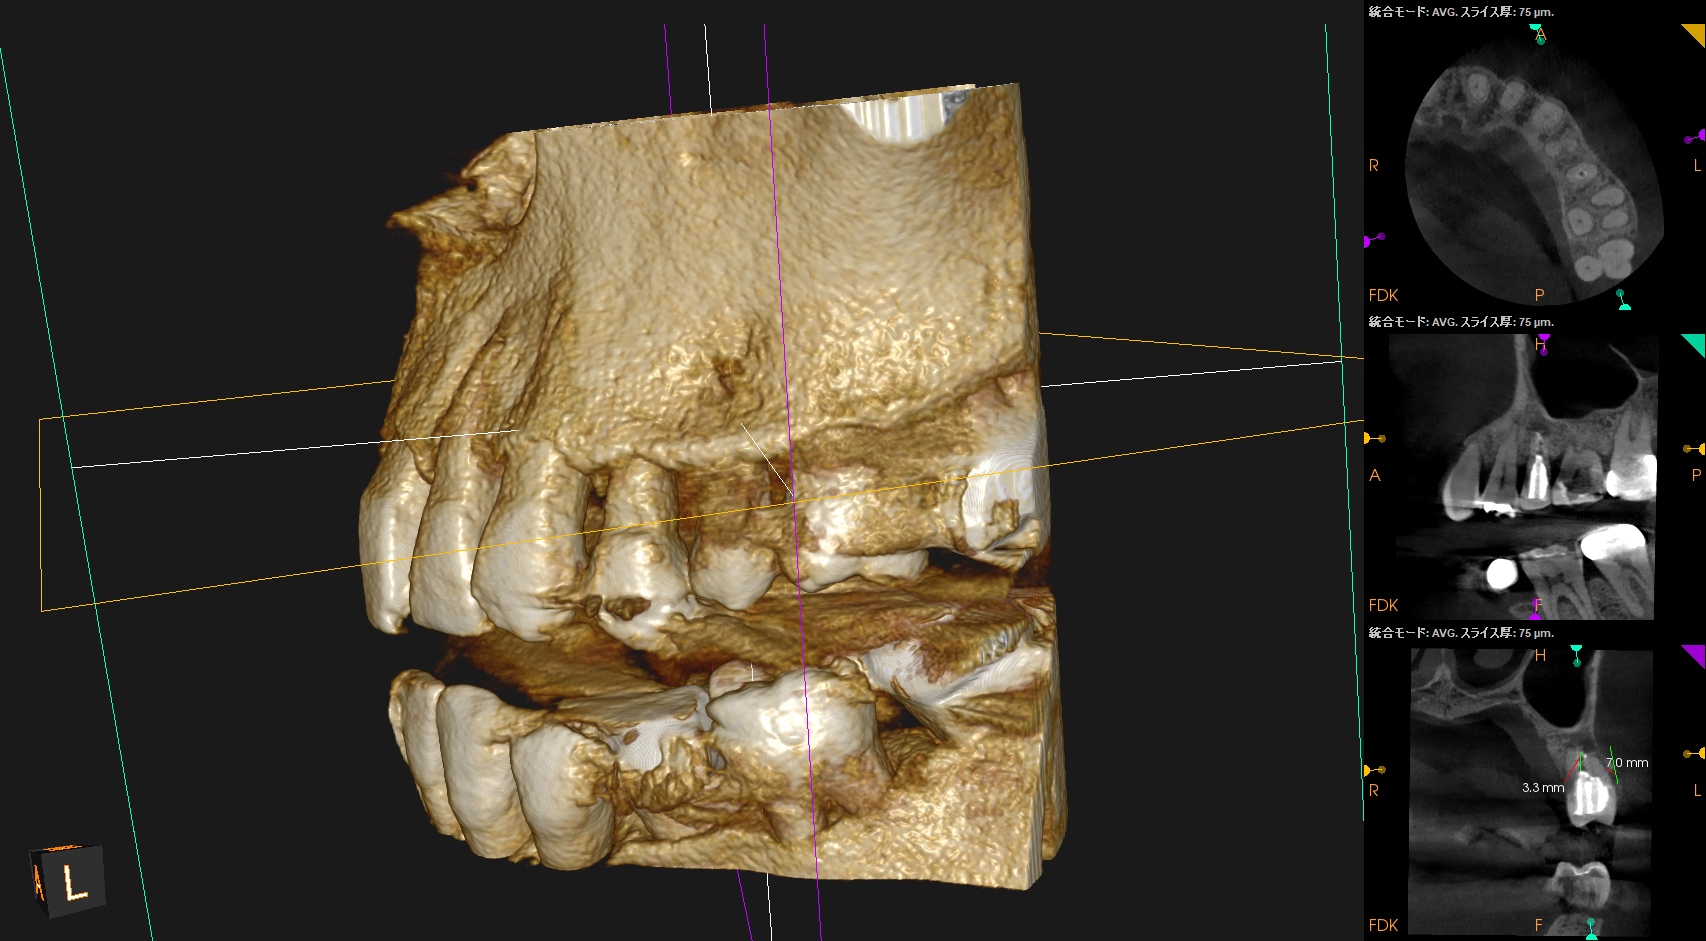

#13 Re-Apicoectomy(2026.4.14)

術後にPA, CBCTを撮影した。

再度、何らかの原因で逆根管充填材が外れないように深く逆根管充填した。

今回の修正は、

逆根充材の厚みを増してみるというその1点のみである。

やはり浅い逆根管充填はそれが外れやすいというリスクがあるようだ、と私はこのケースから感じた。